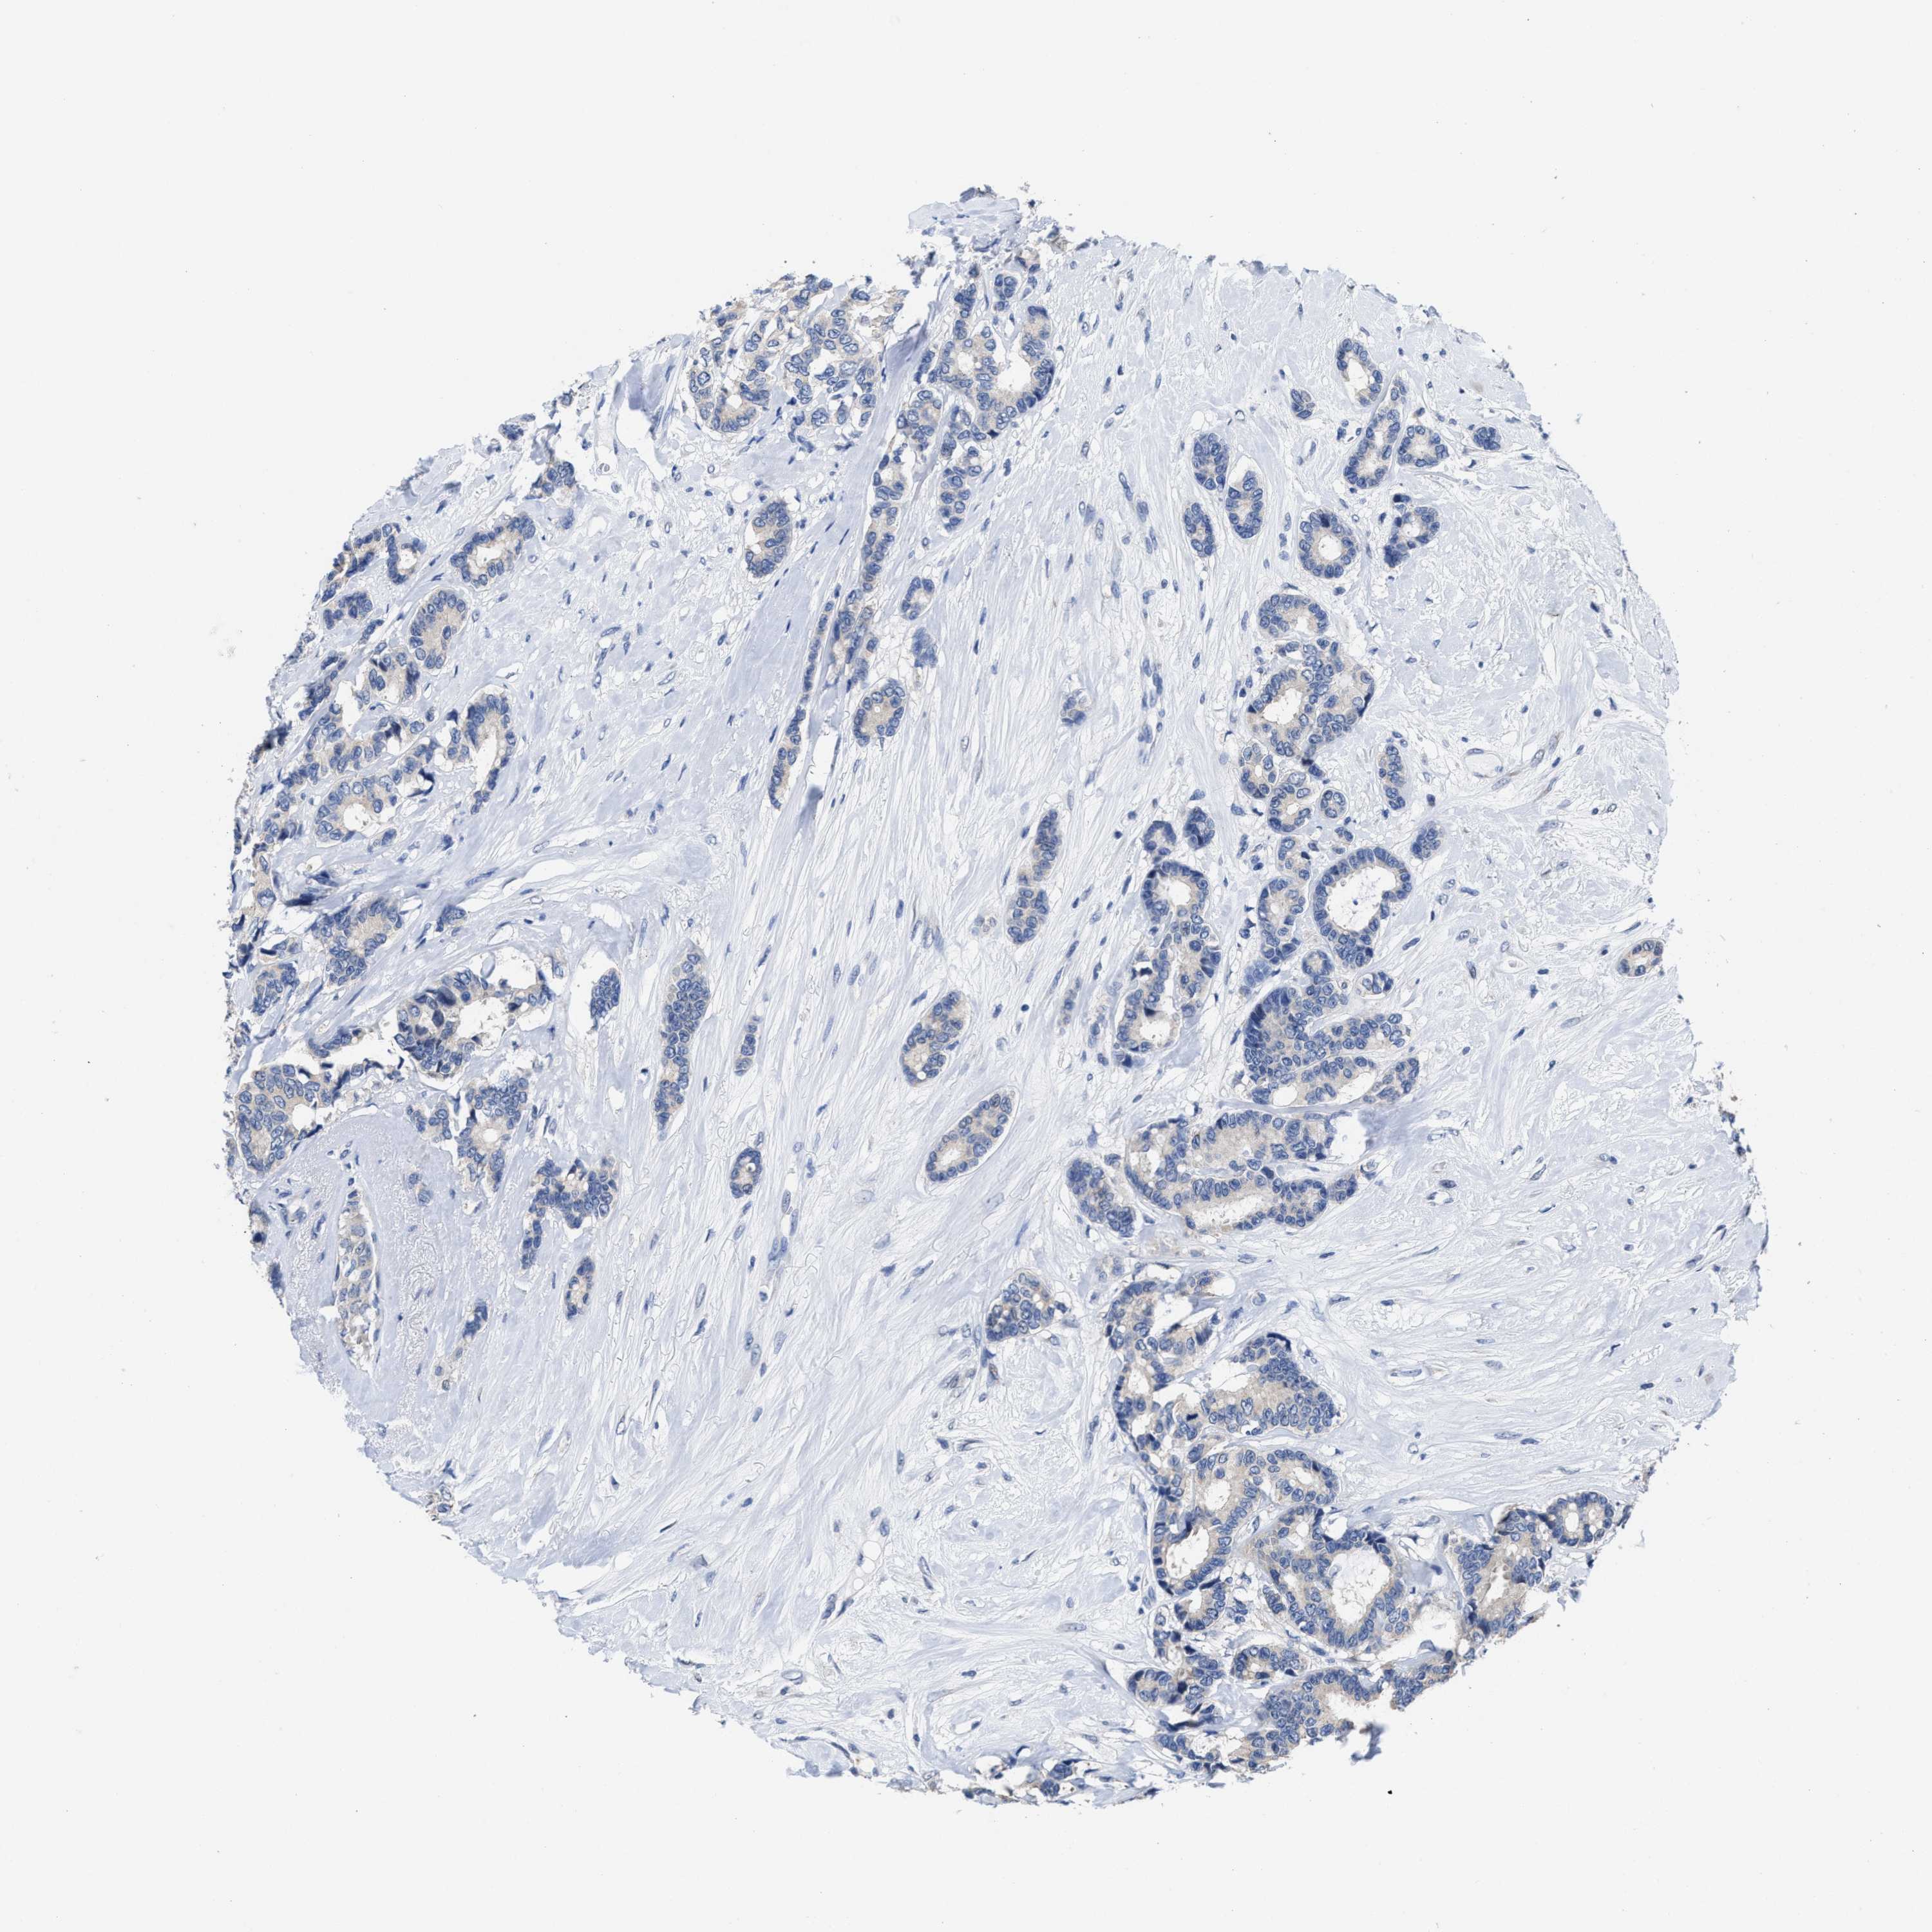

CANCER BREAST CANCER Show tissue menu

Breast cancer

Human cancer